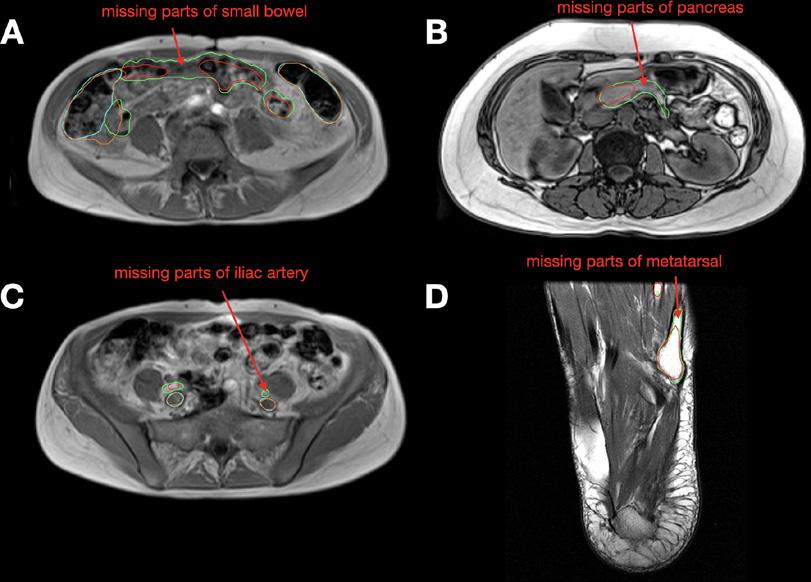

Figura 6. Ejemplos de casos de falla en exploraciones de MRI axiales del conjunto de prueba de MRI. (A) La predicción del modelo de intestino delgado (rojo) tiene partes faltantes en comparación con la segmentación de referencia (verde). La predicción del colon (naranja) sobrepasa la segmentación de referencia (cian). (B) La predicción del modelo de páncreas (rojo) tiene partes faltantes en comparación con la segmentación de referencia (verde). (C) La predicción de la arteria ilíaca (roja) tiene partes faltantes en comparación con la segmentación de referencia (verde). La predicción de la vena ilíaca (naranja) es muy similar a la segmentación de referencia (cian). (D) La predicción del modelo metatarsiano (rojo) tiene partes faltantes en comparación con la segmentación de referencia (verde).